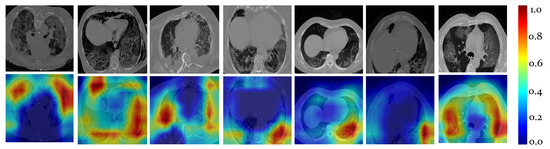

4.1. COVID-19 Quantification for VoI Detection

- Selvaraju, R.R.; Cogswell, M.; Das, A.; Vedantam, R.; Parikh, D.; Batra, D. Grad-CAM: Visual Explanations From Deep Networks via Gradient-Based Localization. In Proceedings of the IEEE International Conference on Computer Vision, Venice, Italy, 22–29 October 2017; pp. 618–626. [Google Scholar]